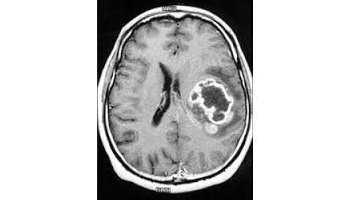

L'imagerie par résonance magnétique (IRM) est une technique d'imagerie médicale permettant d'obtenir des vues 2D ou 3D de l'intérieur du corps de façon non invasive avec une résolution en contraste relativement élevée. L'IRM repose sur le principe de la résonance magnétique nucléaire (RMN) qui utilise les propriétés quantiques des noyaux atomiques pour la spectroscopie en analyse chimique. L'IRM nécessite un champ magnétique puissant et stable produit par un aimant supraconducteur qui crée une magnétisation des tissus par alignement des moments magnétiques de spin. Des champs magnétiques oscillants plus faibles, dits radiofréquence, sont alors appliqués de façon à légèrement modifier cet alignement et produire un phénomène de précession qui donne lieu à un signal électromagnétique mesurable. La spécificité de l'IRM consiste à localiser précisément dans l'espace l'origine de ce signal RMN en appliquant des champs magnétiques non uniformes, des « gradients », qui vont induire des fréquences de précession légèrement différentes en fonction de la position des atomes dans ces gradients.

Il est alors possible de reconstruire une image en deux dimensions puis en trois dimensions de la composition chimique et donc de la nature des tissus biologiques explorés.